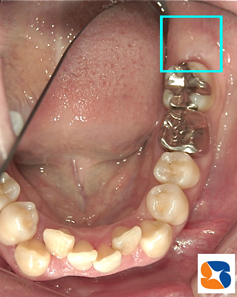

一部分すら見えない親知らずの抜歯 20代の女性。主訴は、「矯正の先生から、親知らずの抜歯依頼」でした。 お口の中を拝見すると、親知らずのどの部分も全く見えていない状態でした。

下あごの骨の中に埋まってる親知らずレントゲンから、親知らずの歯は、下アゴの骨に引っ掛って、出れない状態でした。また、歯の根の先は、90度に折れ曲がり、下アゴの太い神経と癒着している可能性がありました。

下アゴの太い神経と重なる親知らず 30分ほど患者様にはガンバって頂き、無事に抜歯が終了。抜歯後の痛みや腫れは抜歯時間に比例する傾向があるのですが、今日の所用時間なら痛みや腫れは少ないものと思われます。

親知らずの根の先が90度に折れ曲がる抜歯した親知らず。うわーですよね。折れ曲がった歯の根の先もキレイに抜歯が出来ています。 気になる抜歯後の痛みや腫れもほとんど出ず、現在も良好な経過をたどっています。